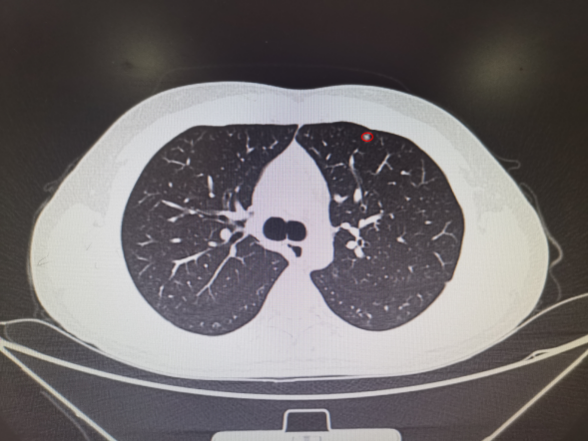

其中消融患者的肺结节位于左肺下叶外基底段24级支气管,膈肌腱部后缘,大小8mm,受呼吸运动影响大,技术难度极大,堪称肺消融治疗的“珠穆朗玛峰”。柳教授团队顺利完成了该例患者治疗,填补了福建省多项肺小结节诊断及治疗技术的空白,同时意味着,那些心肺功能无法耐受开放或者胸腔镜肺小结节手术的患者以及双肺多枚肺小结节需要同时手术的患者有机会获得更多精准且彻底治疗的可能性。

ENB-MWA患者术前小结节位置及消融术后3天复查CT见病灶区域成消融后炎性改变(完全覆盖结节位置)。